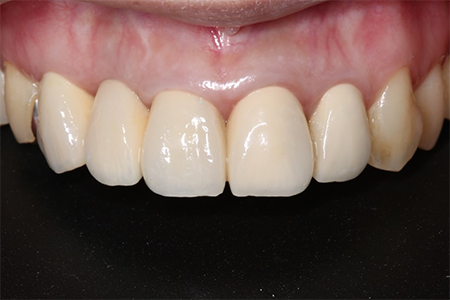

前歯が腫れてしまったと来院された患者様です。

レントゲンを見てみると歯根(歯の根の部分)が黒く溶けていることが分かり、抜歯と診断しました。

前歯のインプラントはとても難しく技術がないと歯茎が下がってしまったりと不具合が出てしまいます。

X-ray

処置後、非常に審美的な補綴物が入ったことが分かるかと思います。